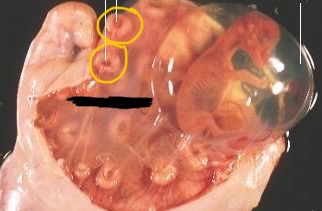

Graafian follicles in ovaries (cow)

Corpora lutea in ovaries (cow)

Caruncles (cow)

Follicles (cow)

CL (cow)